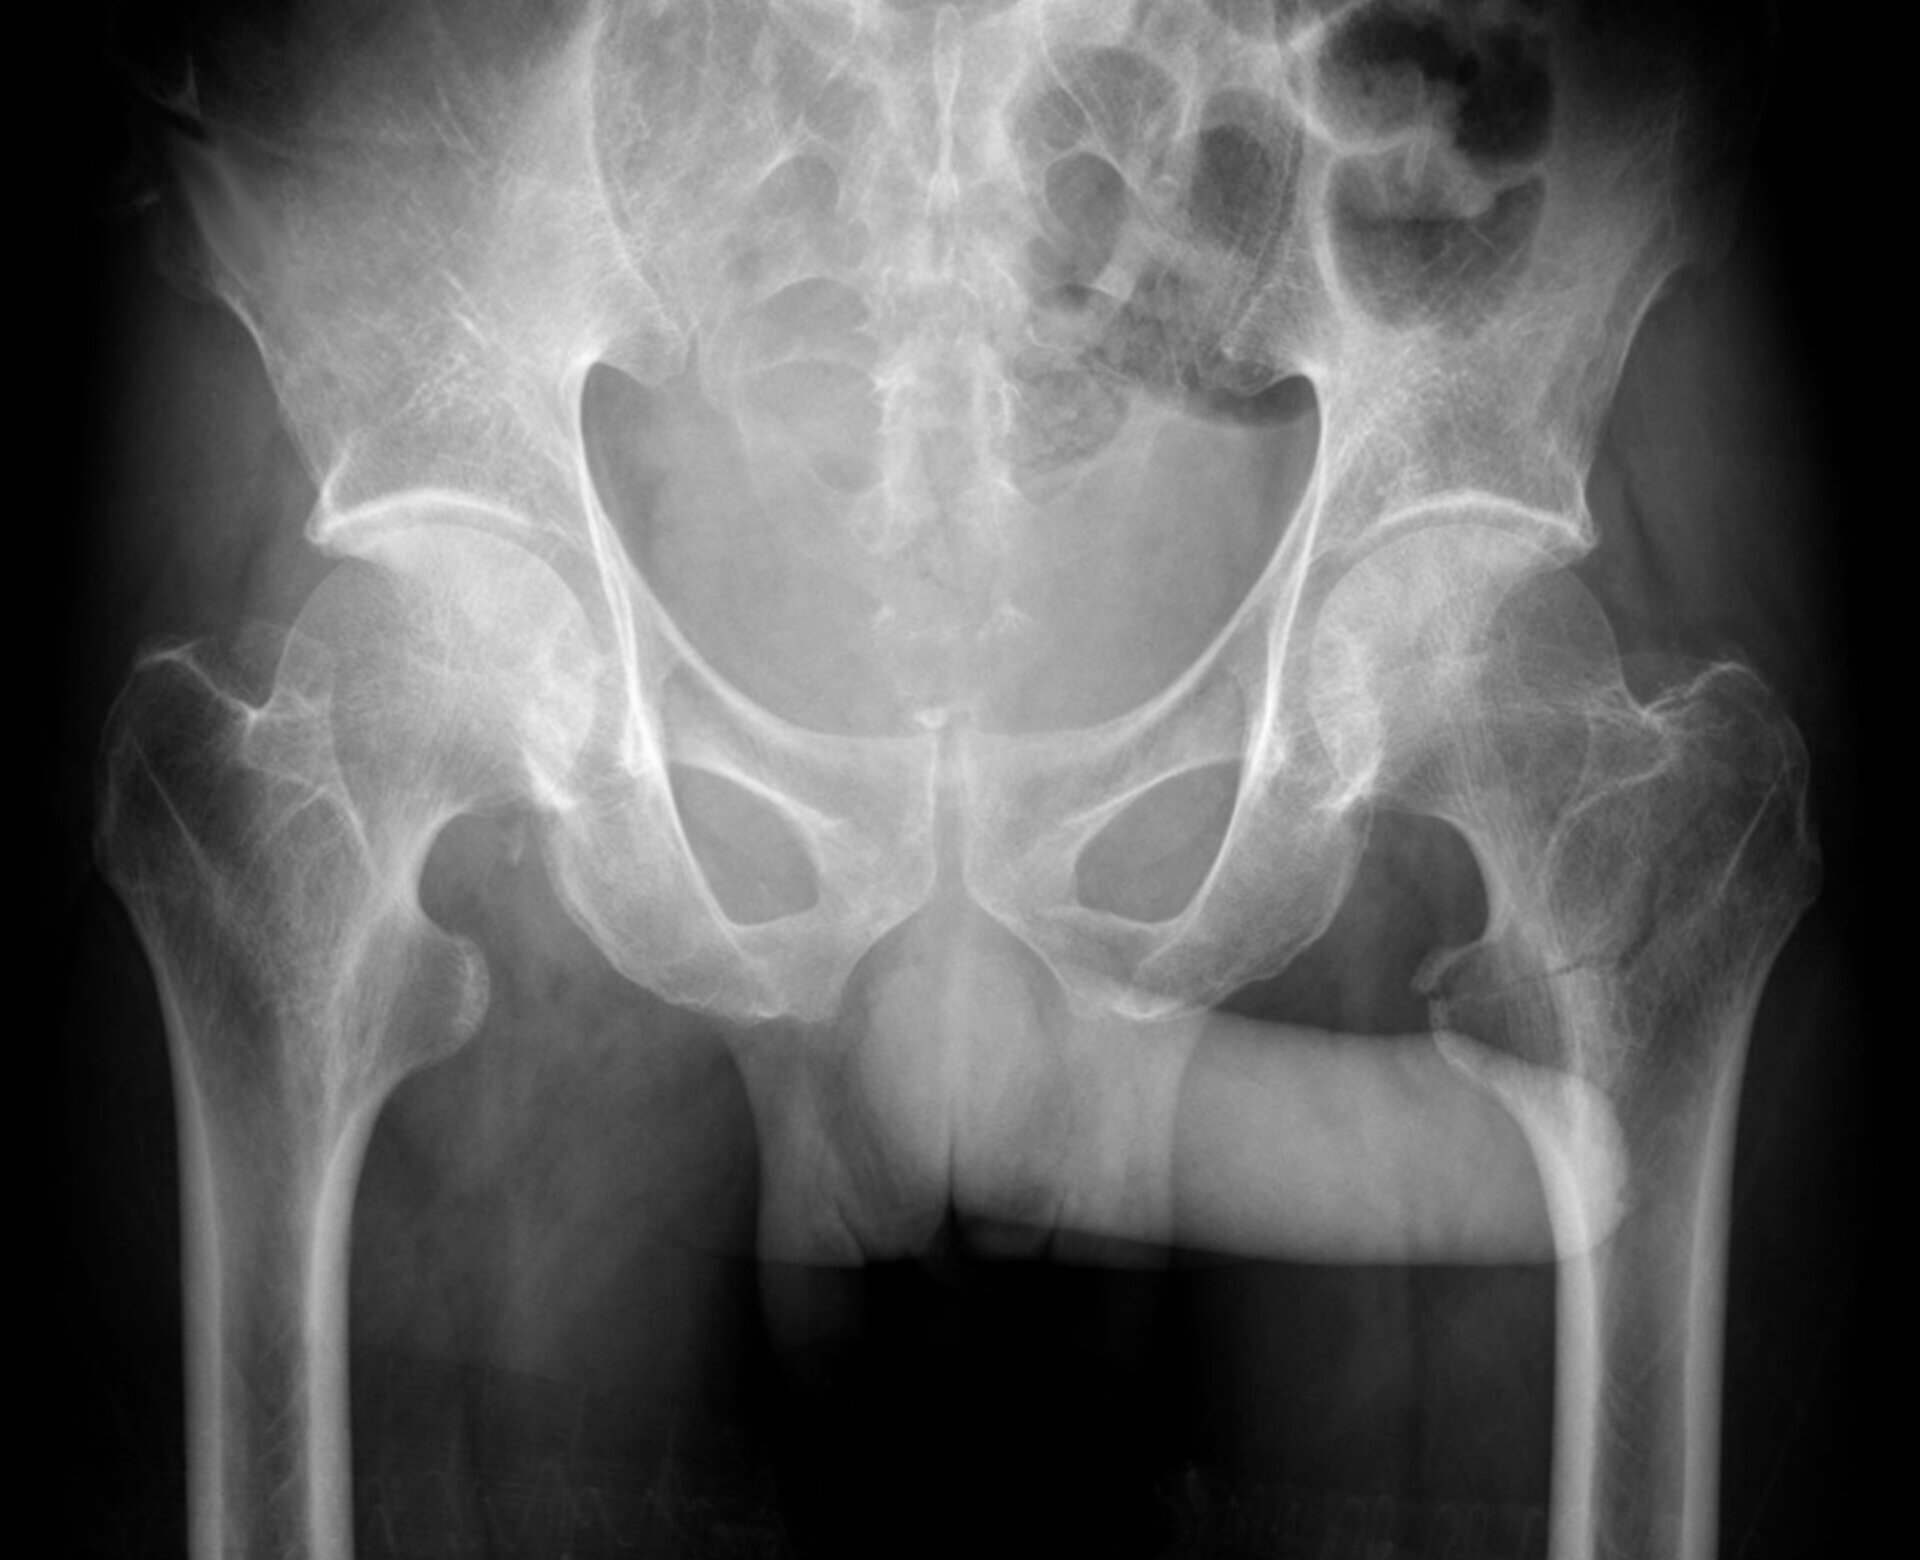

Throkmorton-Zeichen ist eine scherzhafte Bezeichnung für ein radiologisches Zeichen, bei dem der Penis auf einer Röntgen-Beckenübersichtsaufnahme in Richtung einer einseitigen pathologischen Läsion (z. B. Fraktur, Luxation) zeigt. Das Zeichen wird vor allem im Kontext von Verletzungen des Beckens oder der Hüfte erwähnt, hat aber keinen gesicherten diagnostischen Wert.

Bildquelle: Wikimedia Commons // Hellerhoff

Lizenziert unter: Creative Commons Attribution-Share Alike 3.0 Unported